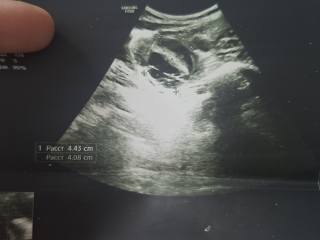

Здравствуйте всем кто читает этот текст,меня зовут Ира мне 18 лет,пол года назад мне поставили диагноз киста яичника,нужна срочная операция, брала